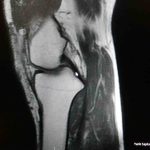

Ortopedi polikliniklerine en sık ayak bileği, diz ve omuz yaralanmalarıyla başvurulduğunu belirten Demirbaş, futbol nedeniyle yaralanma oranlarının da ilk sırada yer aldığını söyledi. Konuya ilişkin Demirbaş, “Futbolda menisküs yırtıkları, ön çapraz bağ yırtıkları, iç ve dış yan bağ yaralanmaları, aşil tendon kopmaları ve ayak bileği bağ yaralanmaları çok sık görülüyor. Ayrıca spora bağlı kırıklar da önemli bir yer tutuyor” ifadelerini kullandı.